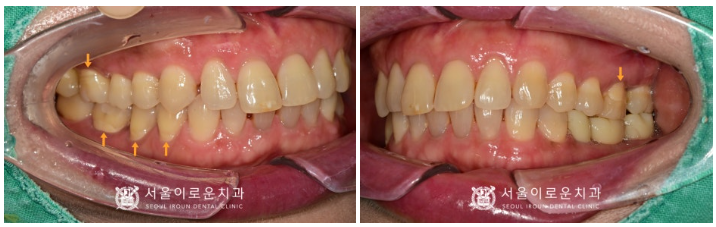

임플란트 / 사랑니 발치

치경부 마모증 / 인레이

치료를 모두 마무리 한 모습입니다.

환.자분께서는

발치 후 임플란트 즉시 식립을 통해

통.증도 사라지고,

치료기간도 단축되어 만.족해하셨고,

시린 증.상이 많이 완화되어

만.족해하셨습니다.

✅ 전 > 후 ✅

(2023.02.02ㅡ>2023.07.15)